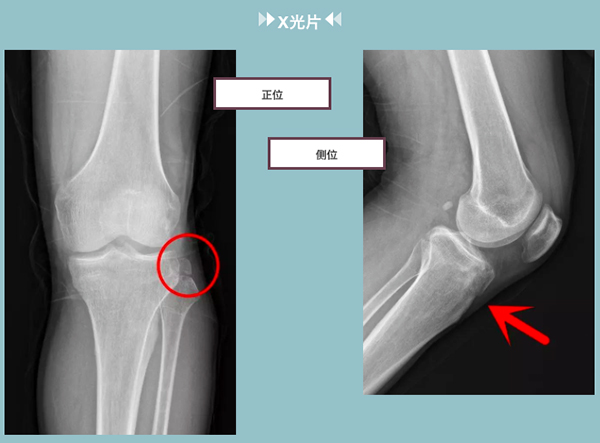

我们看到在第一张正位图像上,已然可以确诊王伯伯左侧腓骨上端撕脱骨折了。

在第二张侧位图像上,箭头指向处,我们可以看见胫骨外侧平台有异于正常结构的透亮线影(我们可以把它想作吐司上的小黑点)此处应高度怀疑骨折!为了不漏诊,我们再加做CT检查。